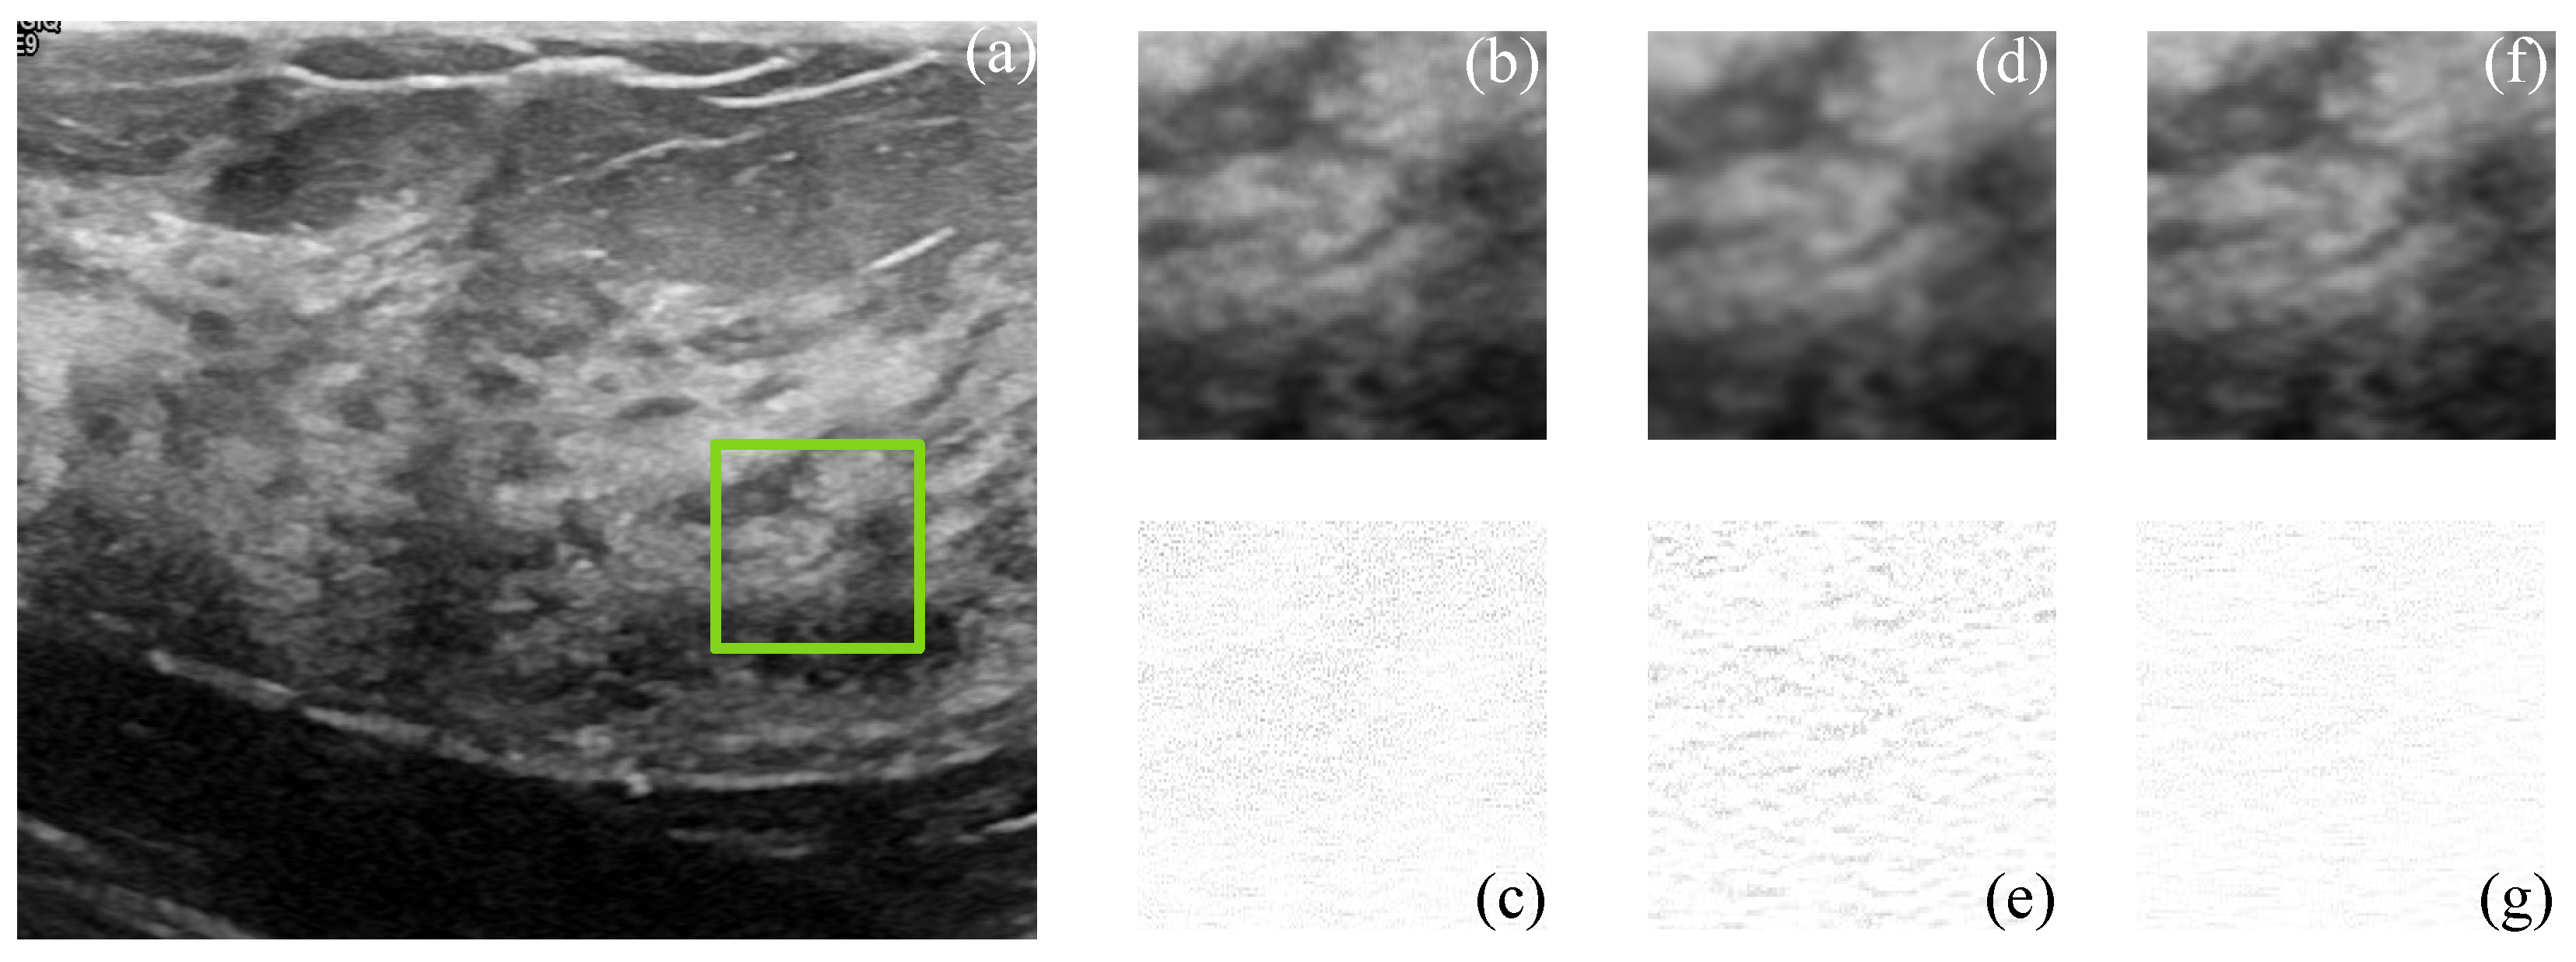

Figure 5 and Figure 6 show the simulated and filtered ultrasound images, indicated as US-sim-04 and US-sim-11, respectively, with the subjective visual comparison with the BM3D and SD-BM3D.

The visual results in Figure 5 and Figure 6 show that the designed framework can achieve good performance for the despeckling procedure. As can be observed, the BM3D technique produces artifacts that degrade the processed images, and the SD-BM3D method tends to over-smooth edges and fine details by comparing the error images. The principal disadvantage of these techniques is that they do not consider the images’ local statistical properties and texture features for grouping the 3D blocks, which limits the denoising performance. The proposed CMI-3DSVD filter outperforms the mentioned denoising methods by preserving important details of the image, such as edges, and by not blurring homogeneous regions.

Figure 6. Subjective visual results of the despeckled simulated US image US-sim-11. (a) Input image. Details are taken from the region marked in green: BM3D: (b) despeckled image, PSNR = 17.02 dB, EPI = 0.3247; (c) error image. SD-BM3D: (d) despeckled image, PSNR = 17.37 dB, EPI = 0.3516; (e) error image. CMI-3DSVD: (f) despeckled image, PSNR = 18.04 dB, EPI = 0.4021; (g) error image.